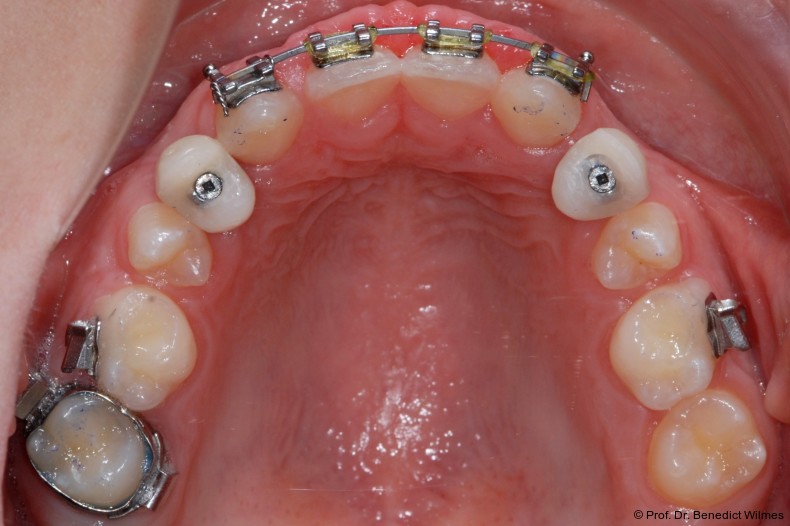

Ein 14-jähriger Patient wurde bei Aplasie der beiden oberen seitlichen Schneidezähne mit dem Ziel der beidseitigen Lückenöffnung kieferorthopädisch therapiert (Abb. 1a+b). Zum Ende der kieferorthopädischen Behandlung wurden zwei Miniimplantate in Regio 2er als temporärer Zahnersatz inseriert (Benefit System, PSM, 2 x 13 mm, Abb. 2a+b). Nach Abdrucknahme wurden Kronen auf den Peek-Abutments modelliert und diese mit Kunststoff auf die Abutments geklebt (Abb. 3a–d). In den Abbildungen 3 und 4 sind die klinischen und röntgenologischen Nachkontrollen innerhalb der nächsten achteinhalb Jahre dokumentiert. Man erkennt einen sowohl in der Höhe als auch in bukkopalatinalen Breite verbleibenden gesunden Knochen ohne Anzeichen einer Atrophie. Im Alter von 23 Jahren wurden die definitiven Implantate ohne die Notwendigkeit einer Augmentation eingesetzt (Abb. 5) und nach Einheilung prothetisch versorgt (Abb. 6a–e und Abb. 7a–c).

Bei einer elfjährigen Patientin fehlten bei Zustand nach Frontzahntrauma im Alter von neun Jahren beide oberen mittleren Schneidezähne (Abb. 8a+b). Als temporärer Ersatz wurden Miniimplantate (Abb. 9, 2 x 13 mm) eingesetzt und Kronen im Labor angefertigt, welche auf den Miniimplantaten verschraubt wurden (Abb. 10a+b). Die Miniimplantate wurden im Alter von 19 Jahren, also nach achtjähriger Nutzung (Abb. 11a+b), durch dentale Implantate ersetzt.

Nach Abschluss der kieferorthopädischen Pfeilerverteilung wurden zwei Miniimplantate in Regio 3er inseriert (2 x 13 mm). Nach Herstellung im Labor wurden Kronen auf den Miniimplantaten aufgeschraubt (Abb. 13+16a–d). Auch hier wurde darauf geachtet, dass die Kronen aus der Okklusion geschliffen wurden (Abb. 14). Bei den Nachkontrollen zeigten sich ebenfalls stabile Miniimplantate und ein entzündungsfreies Implantatlager ohne erkennbare Atrophie des Knochens (Abb. 15 und 16a–d).